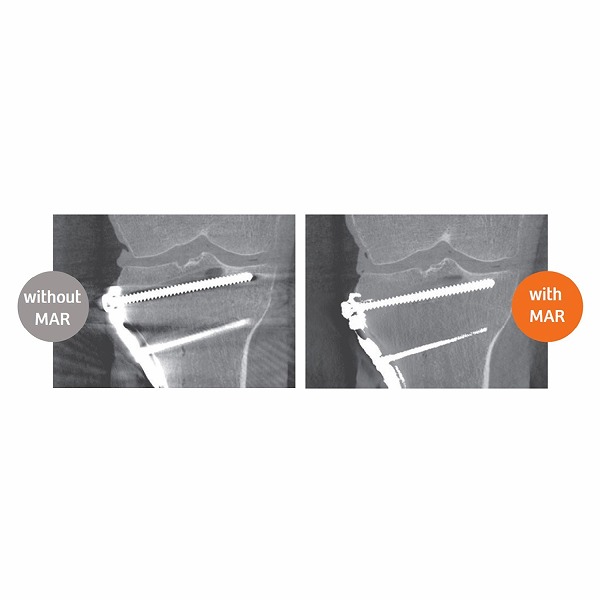

●金属によるアーチファクトを低減させるアルゴリズムを搭載しています。